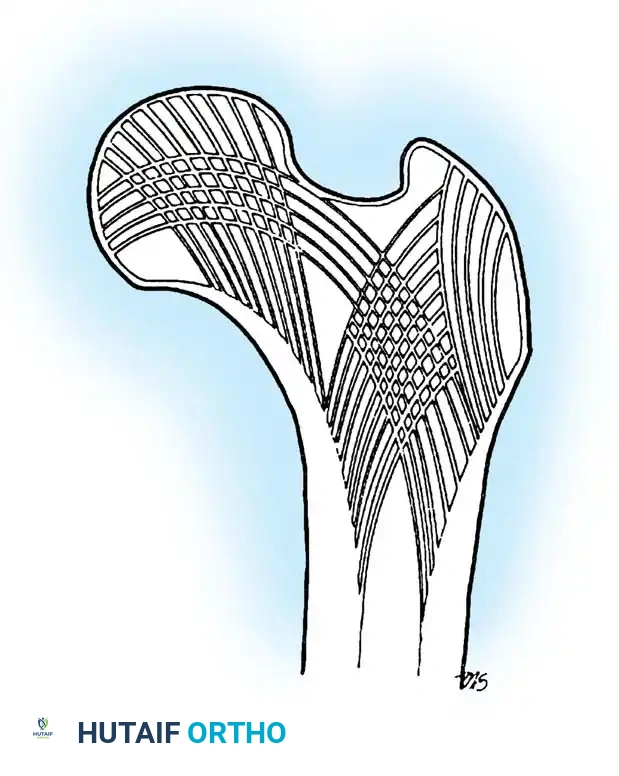

Intertrochanteric fractures occur in the highly vascularized, cancellous bone between the greater and lesser trochanters. Because this region is extracapsular, the blood supply to the femoral head is rarely compromised, making osteonecrosis a rare complication. The primary challenge in treating these fractures is mechanical rather than biological; the goal is to achieve stable fixation that resists the massive deforming forces of the hip musculature until union occurs.

Operative Management: Principles and Biomechanics

Biomechanical Pearl: In reverse obliquity fractures, an SHS is contraindicated. The sliding mechanism of the SHS allows the femoral shaft to medialize uncontrollably due to adductor pull, leading to catastrophic failure. A cephalomedullary nail acts as a lateral buttress, preventing this medialization.